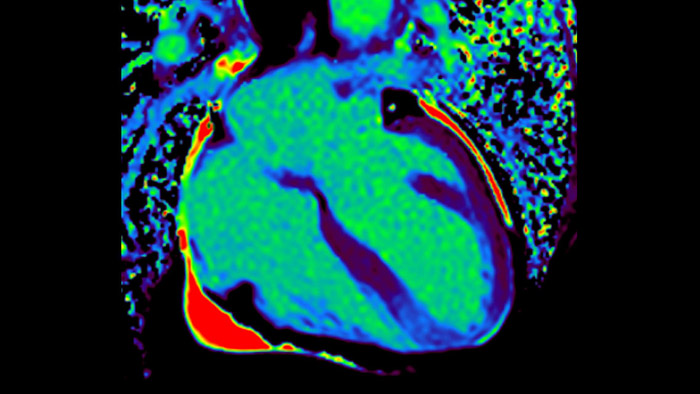

Visualize and evaluate blood flow

Visualise and evaluate blood flow

IntelliSpace Portal MR Caas5,6 4D Flow post-processing solution enables generation of 3D volume reconstructions, to visualise and evaluate blood flow in cardiovascular structures, including heart valves, chambers, and vessels, based on cardiovascular MR 4D Flow imaging.